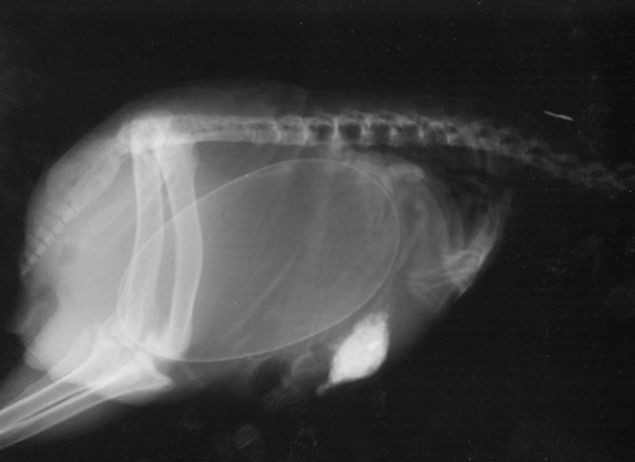

Hayvanların hamilelik görüntüleri yılana bakın! - Resim: 3

Yılan